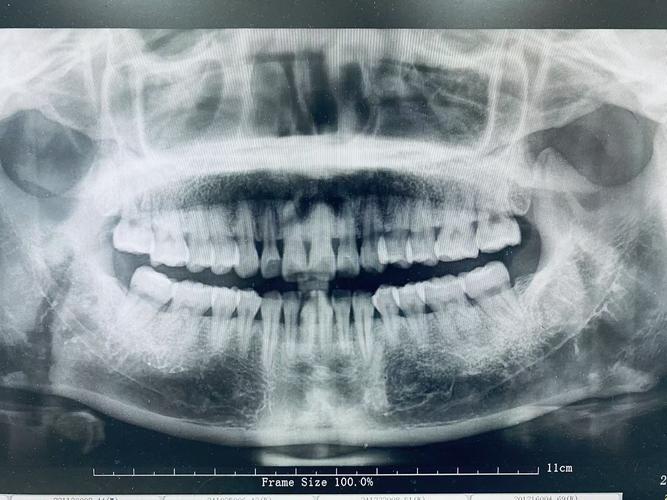

- 全颌曲面断层片(全景片): 最常用、最基础,可以一次性显示上下颌所有牙齿、牙槽骨、部分颌骨、上颌窦、下颌神经管等,是评估牙齿数量、位置、牙根、牙槽骨全景的首选。

- 牙齿数量和位置: 确定是否有缺失牙、多生牙(额外牙)、埋伏牙(未萌出的牙)、阻生牙(位置不正无法萌出的牙),全景片(曲面断层片)是查看全口牙齿排列和位置的基本工具。

- 牙根形态和健康: 观察牙根的长度、弯曲度、有无吸收(牙根变短)、有无根尖病变(牙根尖发炎),牙根吸收在正畸治疗中可能被诱发或加重,治疗前评估至关重要,根尖片(小牙片)常用于观察单颗牙的牙根情况。

- 牙槽骨状况: 评估牙槽骨的高度、厚度和密度,判断牙周支持组织是否健康,这对于牙齿移动的安全范围和长期稳定性至关重要,牙周片(牙片)是评估牙槽骨的金标准。